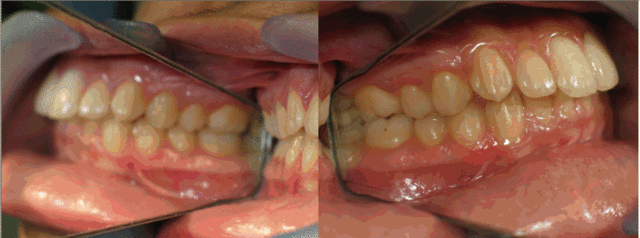

Photos intrabuccales.

04 coted coteg h0mpqk - Eugenol

Comme dsait catrose , il a une proalvélie de départ que tu as bien réduite, mais pas suffisamment. Je me ferai immoler par certains , d'autres peut etre prendront ma défense, mais sans extraction des 4 sup , je vois pas comment tu pouvais la réduire plus que tu as fait.

Les secteurs latéraux, c'est pour moi parfait.

Les rapports verticaux sont supers.

La vue frontale est esthétique.

Le futur au niveau récidives est peut etre un petit zizgag de l'arc incisif supérieur.

L'idéal serait le fil de contention le plus longtemps possible 13-23 et 33-43.